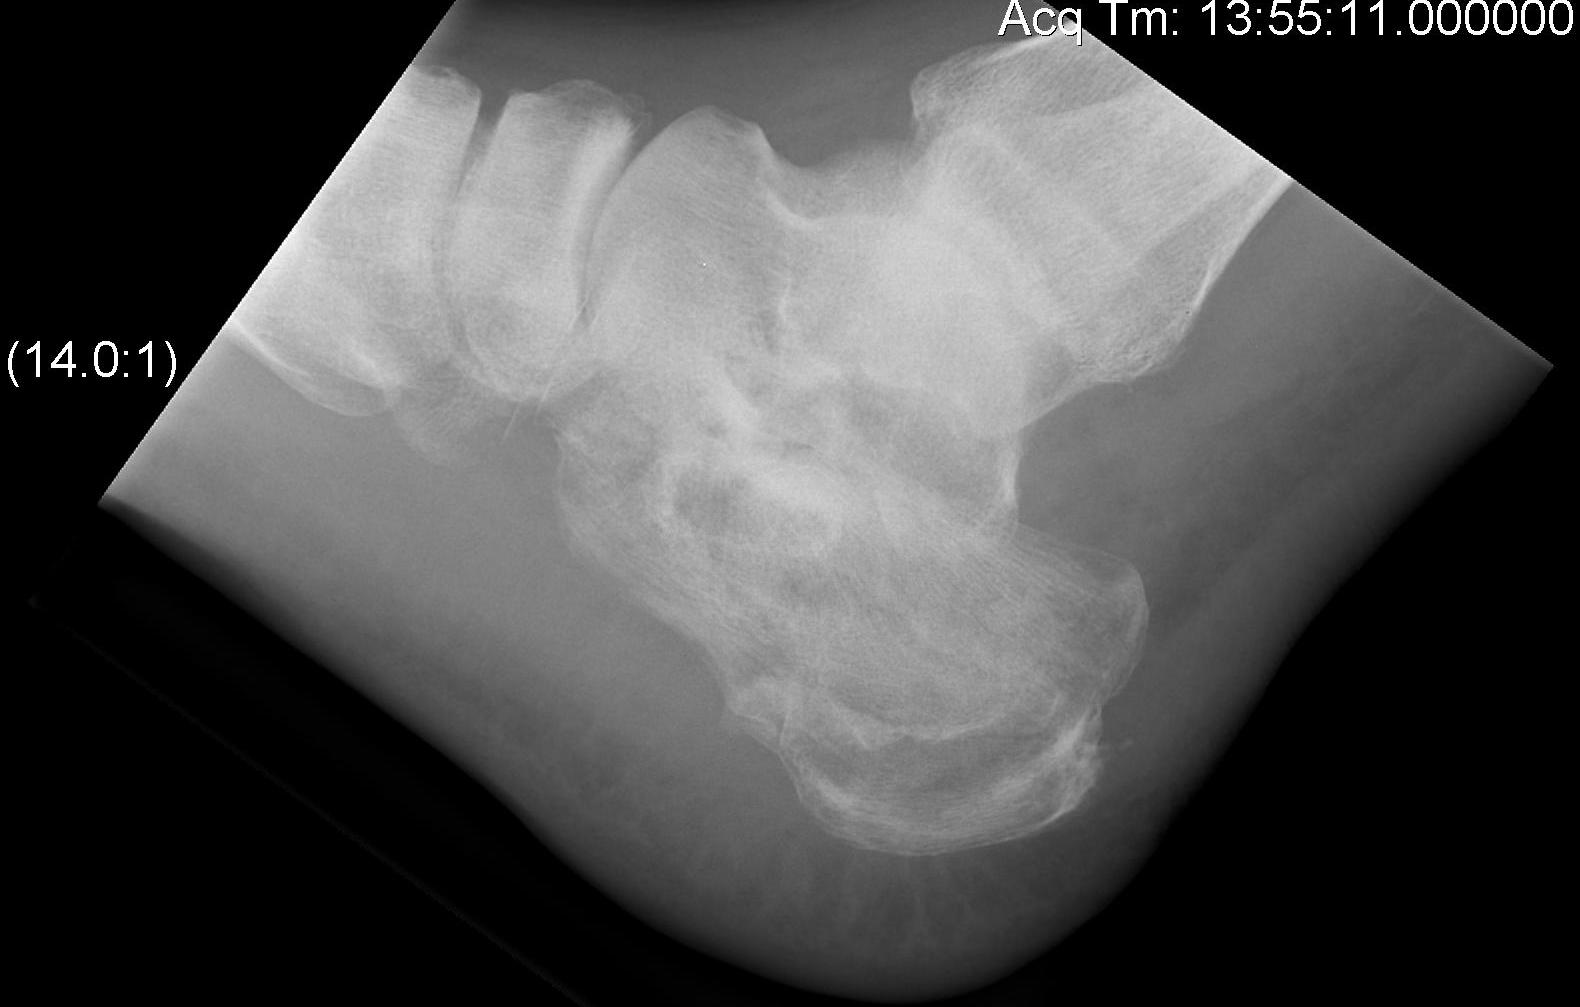

Calcaneal Malunion

Issues

Varus hindfoot - locks midfoot

Peroneal impingement

Shoewear problems

Options

Lateral wall exostectomy and peroneal tenolysis

Calcaneal osteotomy

STJ arthrodesis

Results

Farouk et al Foot Ankle Int 2019

- 18 varus calcaneal malunions

- combined subtalar joint fusion / calcaneal osteotomy / lateral wall exostectomy

- outcome score increased from 60 to 80